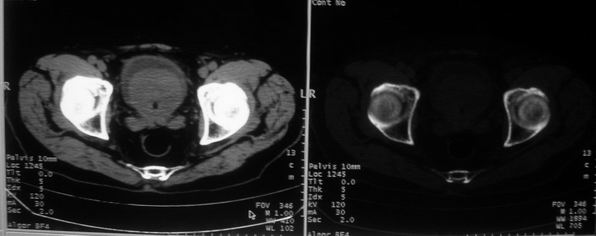

男,85岁,排尿困难。骶椎有问题吗?

前列腺明显增大,突入膀胱,各叶比例协调,密度均匀,精囊腺及精囊角正常;考虑良性增大。

骶骨没有看到明显异常。

1)前列腺明显增大,突入膀胱,各叶比例协调,密度均匀,精囊腺及精囊角正常;考虑前列腺增生症并阻塞性膀胱炎。2)骶椎右侧类似囊状骨质密度减低区,边缘骨质硬化,其内为软组织密度影填塞,相邻之骶椎椎管受压变形;考虑为骶椎右侧囊肿或神经纤维瘤。

建议:行mri检查。